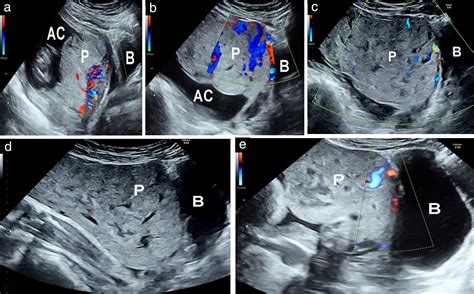

The placenta is a temporary organ that develops in the uterus during pregnancy. It serves as a lifeline between the mother and the fetus, facilitating the exchange of nutrients, gases, and waste products. Lakes In The Placenta refer to small, fluid-filled spaces within the placental tissue. These lakes are not typically visible to the naked eye but can be detected through advanced imaging techniques and histological examinations.

• Ultrasound Imaging: High-resolution ultrasound can sometimes detect the presence of lakes, although this method is not always reliable.

• Magnetic Resonance Imaging (MRI): MRI provides detailed images of the placenta and can help identify lakes more accurately.

• Pregnancy Complications: The presence of lakes has been associated with certain pregnancy complications, such as preeclampsia and intrauterine growth restriction (IUGR).

• Fetal Development: Lakes may influence fetal development by affecting the efficiency of nutrient and gas exchange.

• Maternal Health: The condition of the lakes can also provide insights into the overall health of the mother, as they are influenced by maternal blood flow and immune responses.

• placental lake on ultrasound

• placental lake vs cyst